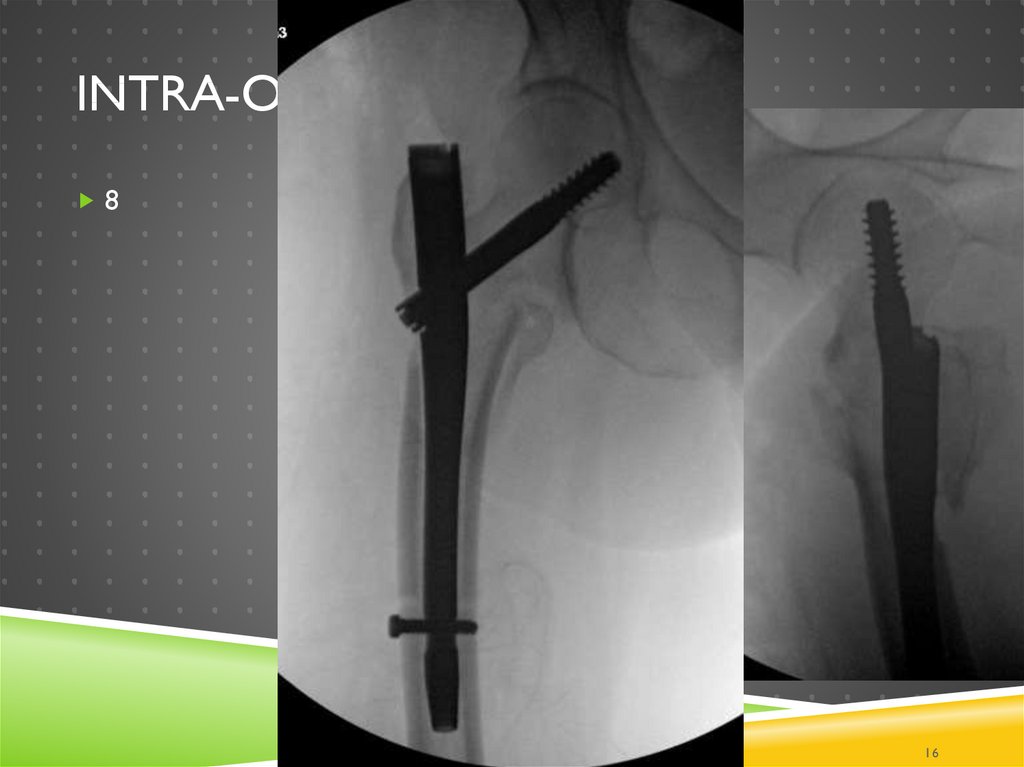

16. Intra-op

INTRA-OP

8

16